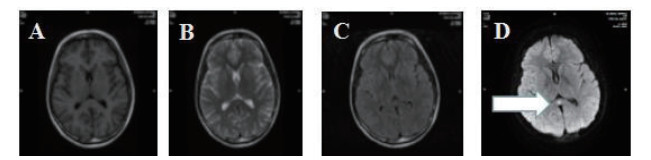

2 结果 2.1 基本资料及头颅核磁特征本观察研究最终纳入患者51例,中毒患者的头颅核磁特征表现为:在MRI的常规序列(T1\T2\FLAIR)病灶显示不明显,但在DWI表现为高信号,ADC值下降呈低信号。病变部位主要是胼胝体的压部(所有阳性病例胼胝体压部均受损),病变也可以形成以胼胝体为中心的广泛白质病变,皮质不受损害。见图 1,2。

| 图 1 A.T1序列/B.T2序列/C.FLAIR序列均无异常;D.DWI系列上为高信号(箭头所示) |

| 图 2 A\C弥散像呈高信号,B\D ADC图呈低信号(箭头所示) |